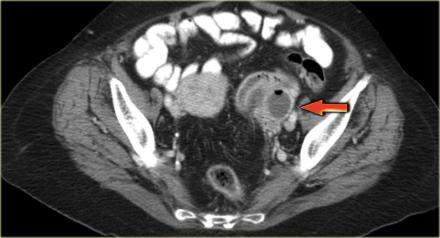

Image 3. CT scan with arrow denoting area of rim-enhancement concerning for TOA. Imagae courtesy of Radiology Assistant https://radiologyassistant.nl/abdomen/ovarian-cysts-common-lesions. Creative Commons license

CT may also demonstrate tuboovarian abscess. It is not the preferred method of diagnosis since it does not evaluate ovarian blood flow and therefore cannot rule out ovarian torsion. CT is frequently ordered in patients to evaluate for appendicitis or other suspected etiology and the scan reveals tuboovarian abscess instead. This CT reveals a complex ovarian mass, consistent with a TOA.